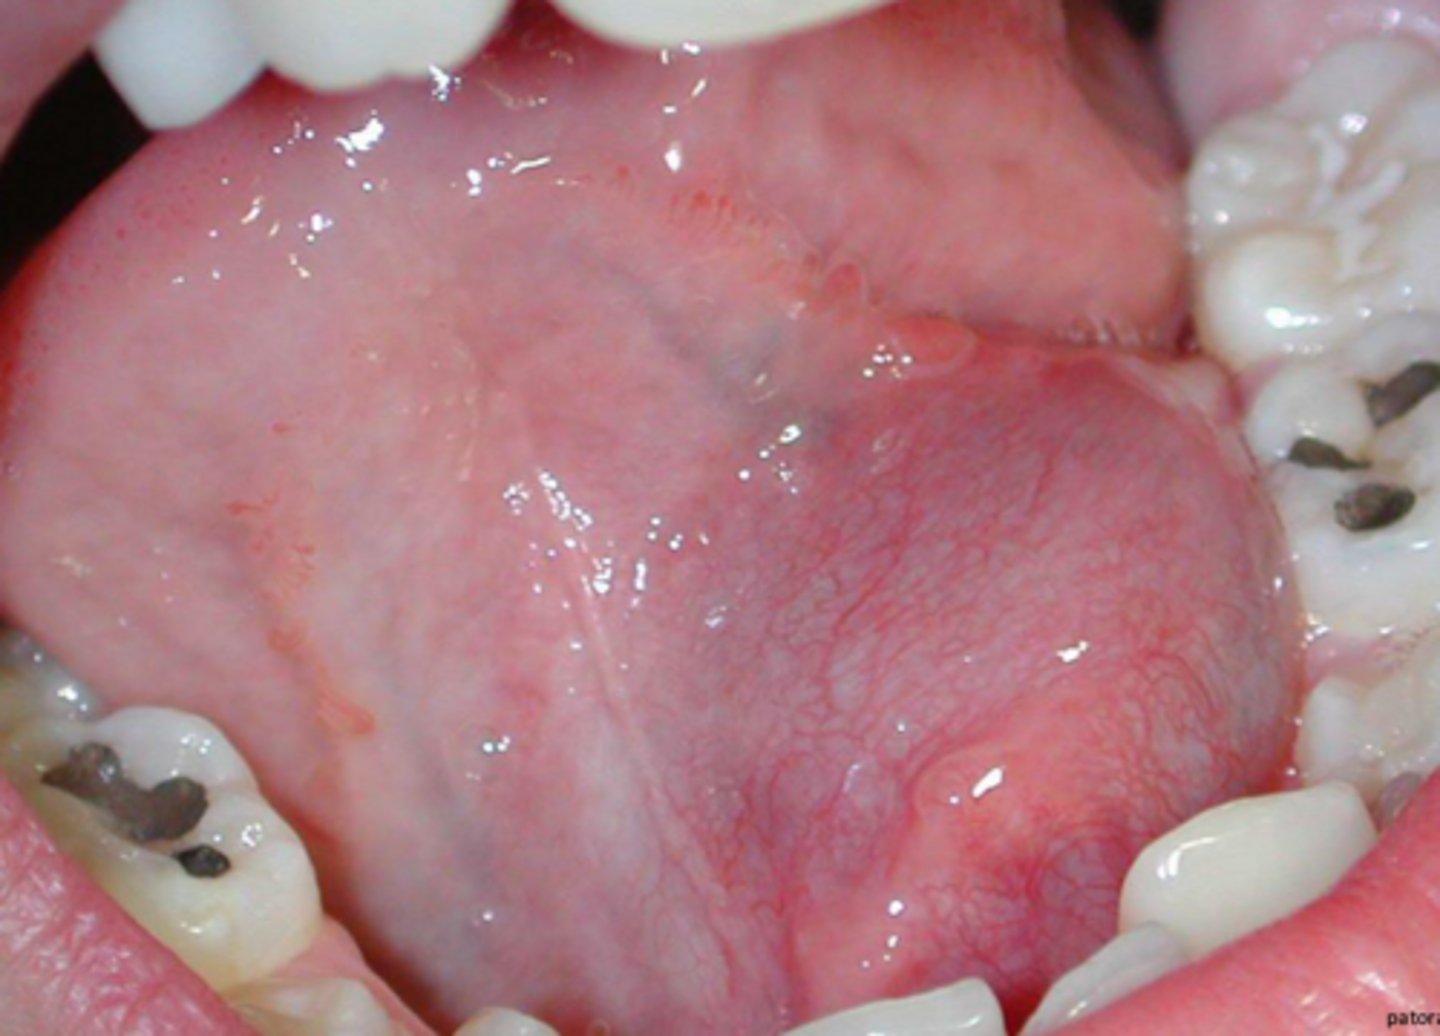

what term refers to mucoceles that occur in the floor of the mouth usually caused from the sublingual gland, usually lateral to the midline?

ranula

(t/f) ranulas tend to be smaller than other mucoceles

false; ranulas tend to be larger than other mucoceles

how are ranulas treated?

removing the feeding gland